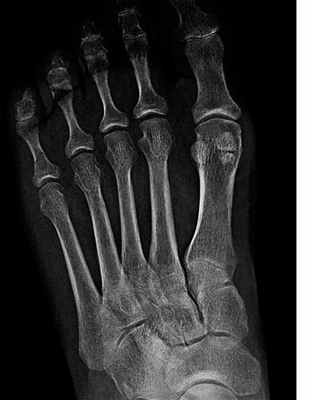

Кости стопы

Рис. 2. Рентгенограмма правой стопы. По внутреннему краю расположена большеберцовая или медиальная сесамовидная кость, по наружному краю – малоберцовая или латеральная сесамовидная кость